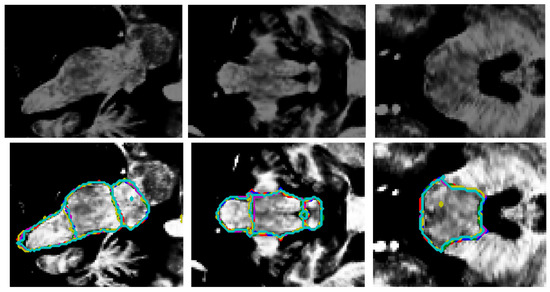

- Superior Segmentation Performance: The proposed modified U-Net architecture (with attention-enhanced skip connections and inception modules) significantly outperforms three comparative approaches in brainstem parcellation, achieving higher scores across all substructures (medulla, pons, and mesencephalon) and the whole brainstem.

- Volume Differences Across Groups: Automated segmentation reveals distinct volumetric patterns, with controls exhibiting larger volumes (whole brainstem: 1.62) compared to preclinical (1.49) and patient groups (1.12), suggesting potential atrophy linked to disease progression.

- Clinical Utility: The method’s accuracy and robustness support its potential for precise brainstem assessment in neurodegenerative disorders, enabling earlier detection of structural changes (e.g., reduced medulla volume in patients: 0.26 vs. 0.31 in controls).

| Label | Mean DSC ± stdev | ||||

|---|---|---|---|---|---|

| This Research | Cabeza-Ruiz et al. [54] | Han et al. [38] (Modified) | Magnusson et al. [69] | Nishimaki et al. [40] (Modified) | |

| Mesencephalon | 0.96 ± 0.022 | 0.92 ± 0.019 | 0.93 ± 0.019 | 0.89 ± 0.031 | 0.91 ± 0.022 |

| Pons | 0.96 ± 0.015 | 0.94 ± 0.014 | 0.94 ± 0.013 | 0.91 ± 0.029 | 0.93 ± 0.014 |

| Medulla | 0.95 ± 0.021 | 0.93 ± 0.020 | 0.92 ± 0.021 | 0.91 ± 0.023 | 0.93 ± 0.021 |

| Full brainstem | 0.96 ± 0.008 | 0.95 ± 0.008 | 0.95 ± 0.007 | 0.93 ± 0.013 | 0.95 ± 0.007 |